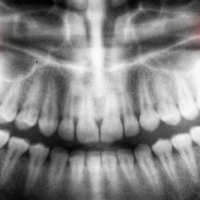

We all feel ashamed sometimes of the misalignment of teeth. That is why we need some impactful solution for it. Braces are one of the most valuable techniques for this type of situation. Your dentist may recommend braces for your pearly whites. At that time, one query that may arise in your mind is: Do braces stain teeth? Well, with braces, it is very difficult to clean teeth properly. Cleaning those tricky, hard-to-reach surfaces becomes challenging when the brackets on braces are in place.

The presence of brackets can make it more difficult to ensure thorough cleaning, requiring extra care to maintain oral hygiene and address those inaccessible areas effectively. So, at that time, braces became the cause of staining on teeth. If you are worried about this type of situation, then don’t panic. This guide is for you. In this guide, we will discuss the reasons as well as treatment for this type of situation. So, without wasting your time, let’s delve into the answer to your query: Do braces stain teeth?